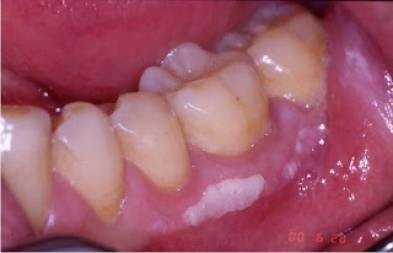

لثه های سفید اغلب ناشی از بیماری به نام لکوپلاکیا هستند. لکوپلاکیا به عنوان بیماری تعریف می شود که در آن لکه ها یا ضایعات ضخیم و سفید روی لثه ها، قسمت داخلی گونه ها و کف دهان ایجاد می شوند و دهان، دندان های لق و زبان را تحت تأثیر قرار می دهد. آنها حتی می توانند روی زبان نیز تشکیل شوند. این لکه های سفید را نمی توان مالش داد یا تراشید.

در حالی که دنیای پزشکی مطمئن نیست که دقیقاً چه چیزی باعث لکوپلاکیا می شود، مصرف دخانیات به هر شکلی و سوء مصرف مزمن الکل به عنوان دلایل احتمالی مشکوک هستند. دندان مصنوعی که به زبان یا داخل گونه های شما ساییده می شود، یکی دیگر از عوامل احتمالی است.

وجود لکوپلاکیا در واقع می تواند نگران کننده باشد، زیرا در حالی که اکثر موارد آن خوش خیم هستند، درصد کمی می تواند نشانه اولیه سرطان باشد و ممکن است نشان دهنده شرایط پیش سرطانی مانند سرطان دهان باشند. این وضعیت پیش سرطانی به عنوان دیسپلازی شناخته می شود. طبق گفته انجمن سرطان آمریکا، دیسپلازی به خفیف، متوسط یا شدید درجه بندی می شود. تعیین درجه دیسپلازی شما، درمان شما را هدایت می کند زیرا دیسپلازی شدید احتمال بیشتری دارد که به سرطان تبدیل شود، در حالی که دیسپلازی خفیف ممکن است به طور کامل از بین برود.

این امر بویژه در صورتی اهمیت دارد که ضایعات قرمز همراه با لکه های سفید باشند، زیرا این موارد بیشتر احتمال دارد که نشان دهنده شرایط پیش سرطانی یا موارد سرطان دهان باشند. درمان لکوپلاکیا ممکن است از بین بردن لکه ها از طریق انجماد، جراحی یا لیزر تا داروهای ضد ویروسی که برای موارد سیستم ایمنی ضعیف مانند عفونت های قارچی توصیه می شوند، متغیر باشد. با این حال، به خاطر داشته باشید که علیرغم درمان، لکوپلاکیا ممکن است به طور قابل توجهی دوباره عود کند.